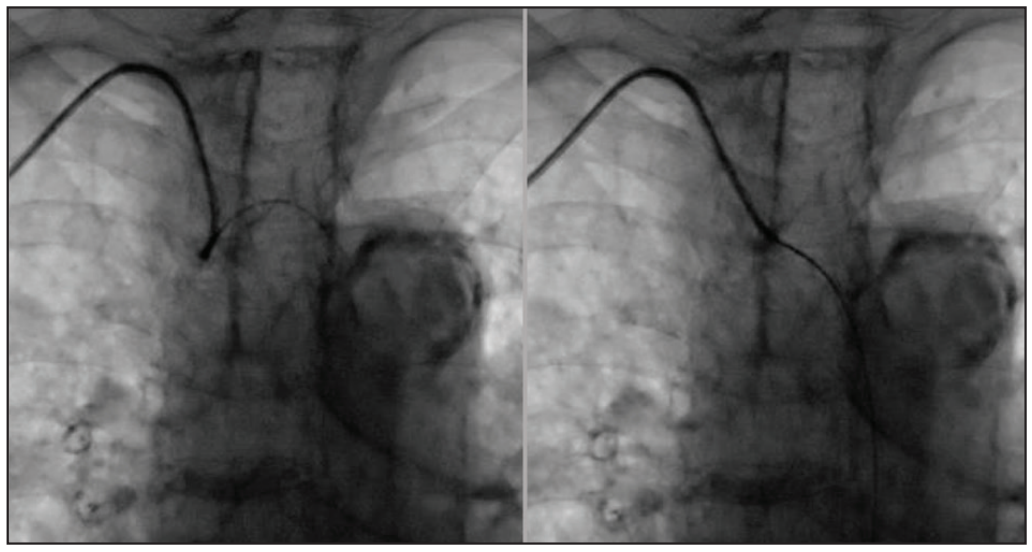

An 84-year-old woman was referred for transcatheter aortic valve replacement (TAVR) without cardiovascular risk factors, except for remote tobacco abuse more than 30 years earlier. She had been diagnosed with aortic stenosis (AS) and managed conservatively by means of annual echocardiographic assessment for the previous 5 years. Approximately 2 weeks prior to consultation, she was admitted with flash pulmonary edema that was treated with diuretics. At the time of consultation, the patient was stable without angina or lightheadedness. The patient lives by herself and is able to perform her activities of daily living. Her medical history included lung cancer (stage IB) treated 8 years earlier with image-guided robotic stereotactic radiosurgery (CyberKnife, Accuray Incorporated), chronic lung disease with an FEV1 40% of predicted without improvement with bronchodilators and an O2 saturation decrease of 89% after walking 700 feet, hypertension, and osteoporosis. Her renal function was preserved with a glomerular filtration rate of 84 mL/min and a creatinine of 0.56 mg/dL. Physical examination revealed that she was a thin and frail-appearing woman with a body mass index of 22.26 kg/m2 (height, 152 cm; weight, 51 kg) who uses a walker to ambulate. The lungs were clear to auscultation. She had a 2/6 crescendo-decrescendo systolic murmur that obscured S2. Echocardiography revealed severe AS with a valve area of 0.58 cm2, aortic maximum/mean pressure gradients of 108.6/72 mm Hg, and a peak aortic valve velocity of 5.21 m/s (Figure 1). There was no aortic regurgitation. The ejection fraction was preserved (65%) and there was severe mitral annular calcification causing mild mitral stenosis (valve area, 1.8 cm2). Coronary angiography demonstrated nonobstructive coronary artery disease. Of note, coronary angiography was performed via right transradial access and significant subclavian tortuosity was encountered while advancing the J-wire, but the vessel straightened, posing no added difficulties to performing the procedure (Figure 2). Hemodynamic assessment showed a peak aortic gradient of 104 mm Hg with an aortic valve area of 0.34 cm2 (Fick principle) (Figure 1). The pulmonary arterial pressure was 48/18/(29) mm Hg. Based on the type of procedure and patient data, the Society of Thoracic Surgeons (STS) predicted risk of mortality was 11.6%.